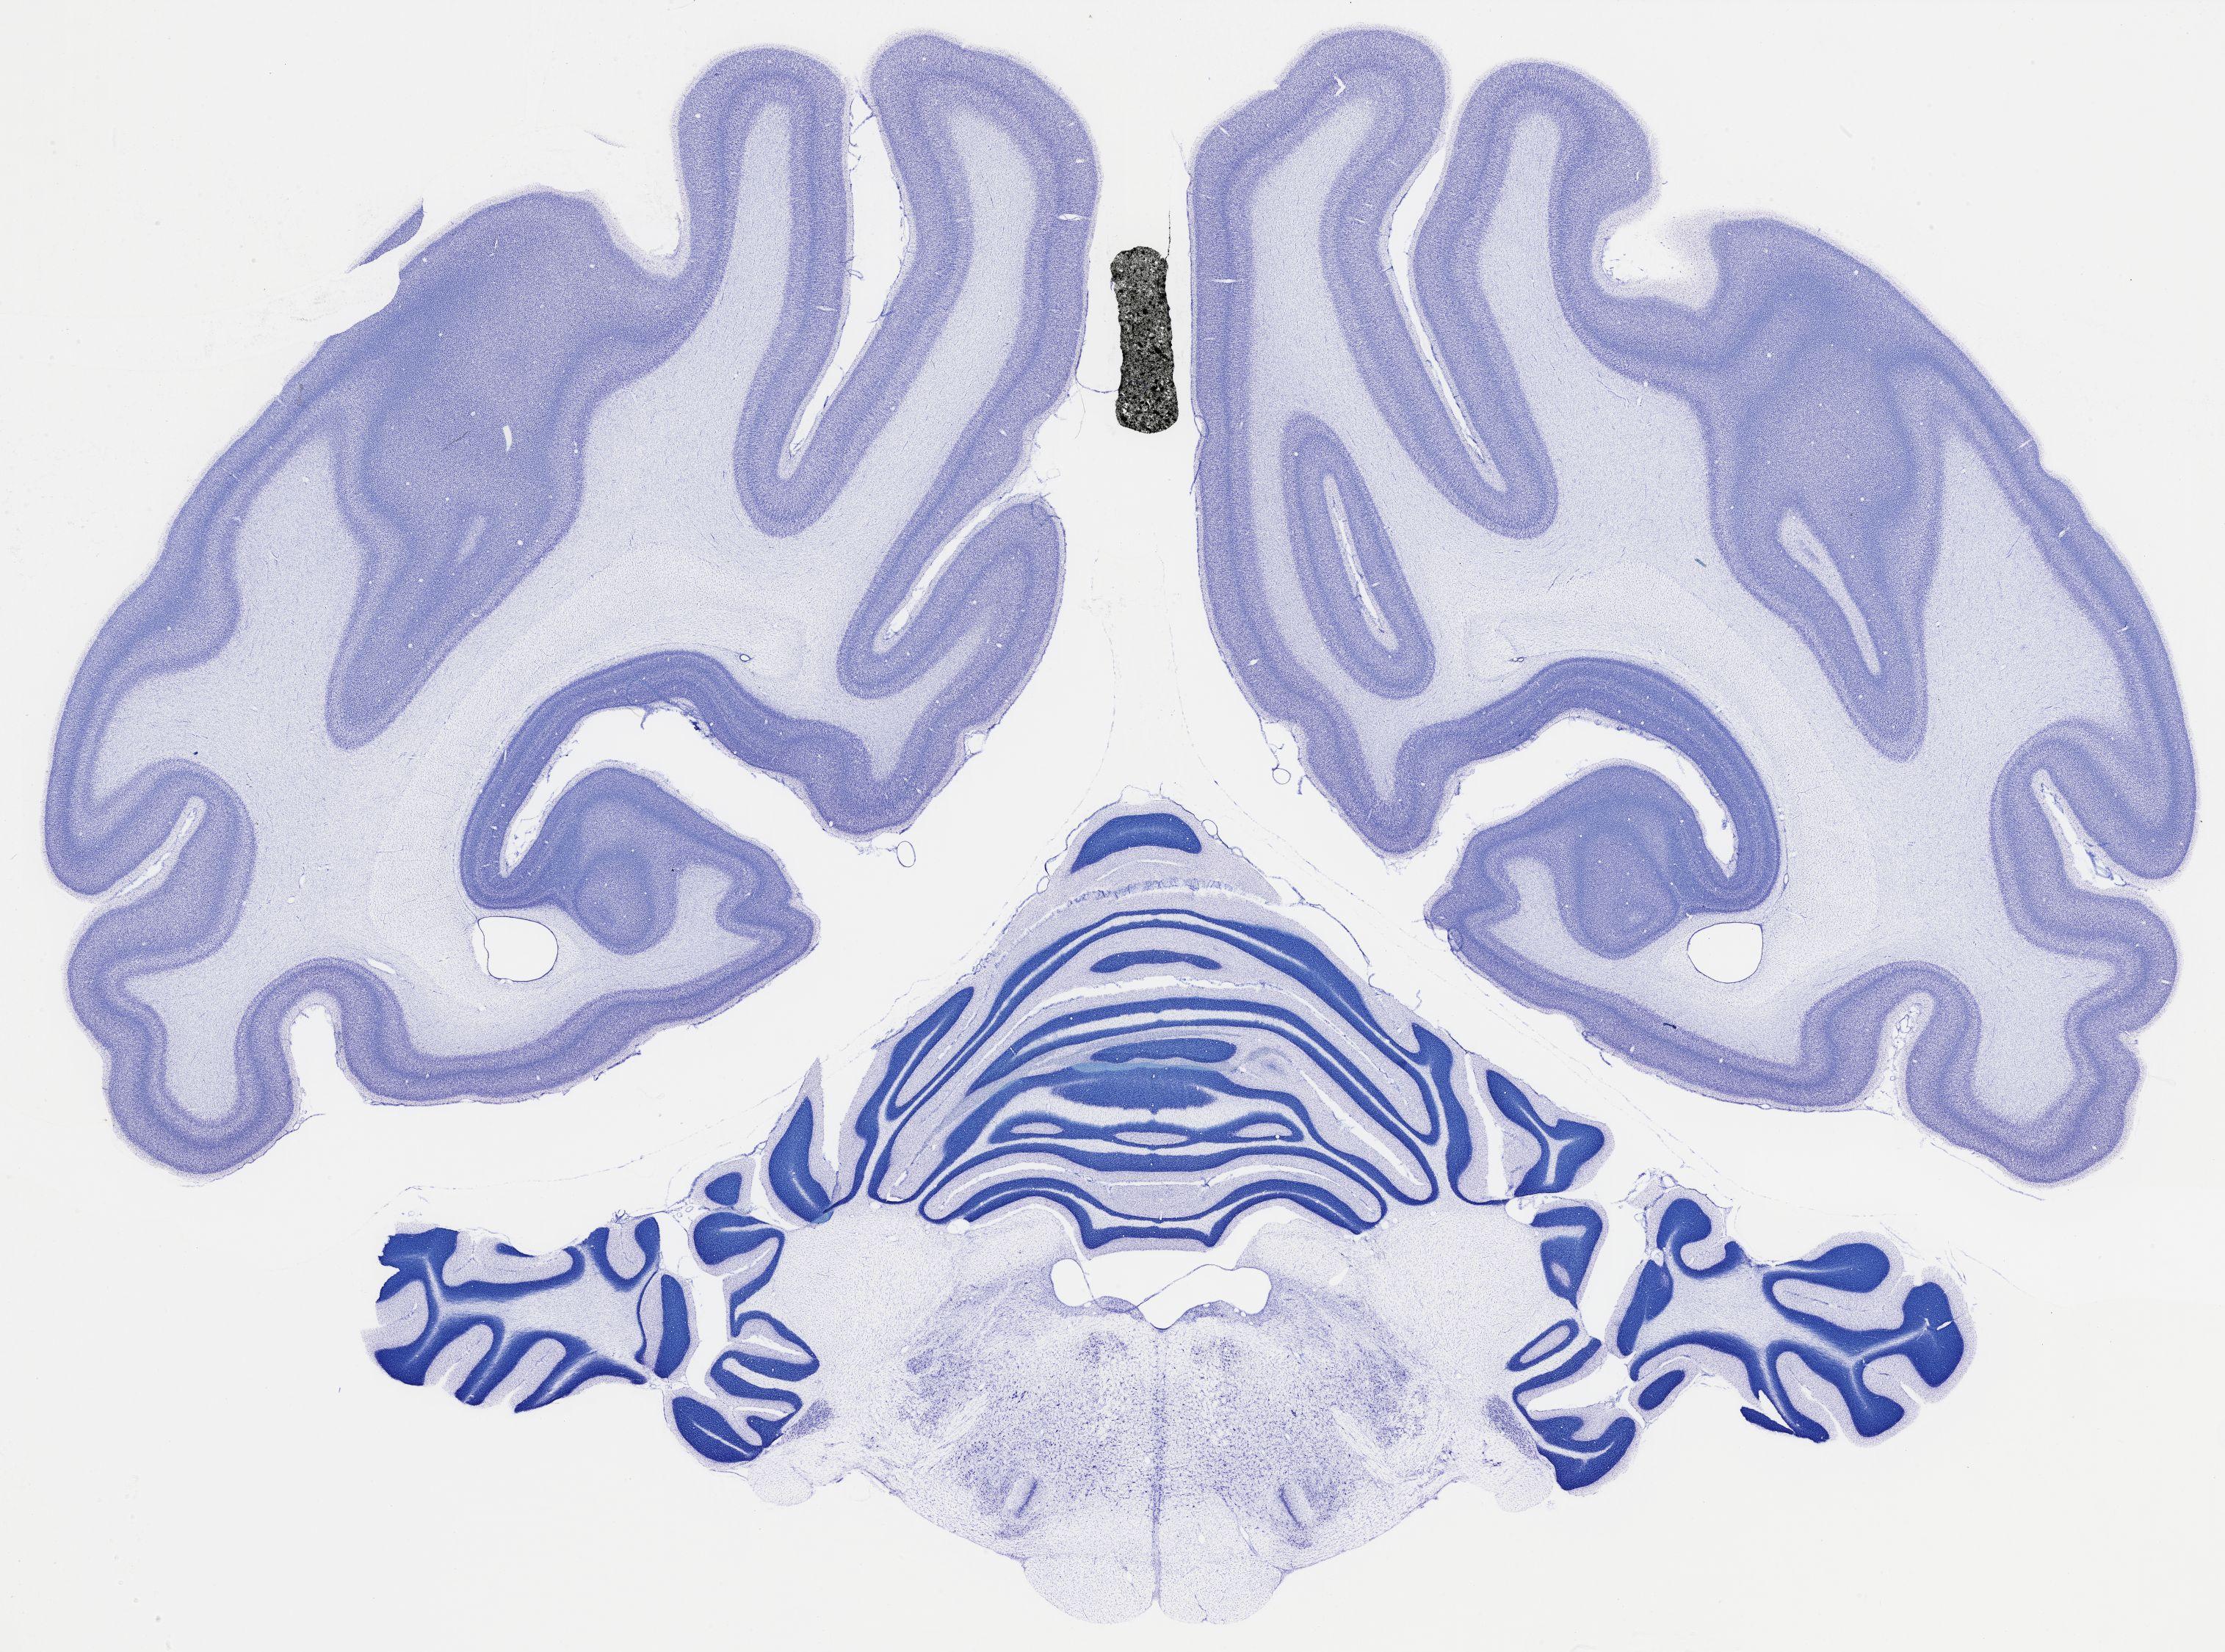

Datasets -> Chlorocebus Aethiops -> Nissl, coronal, histo, Whole-Brain, adult

[ Metadata ]   ·   Source: NeuroScience Associates

thumbnail

523